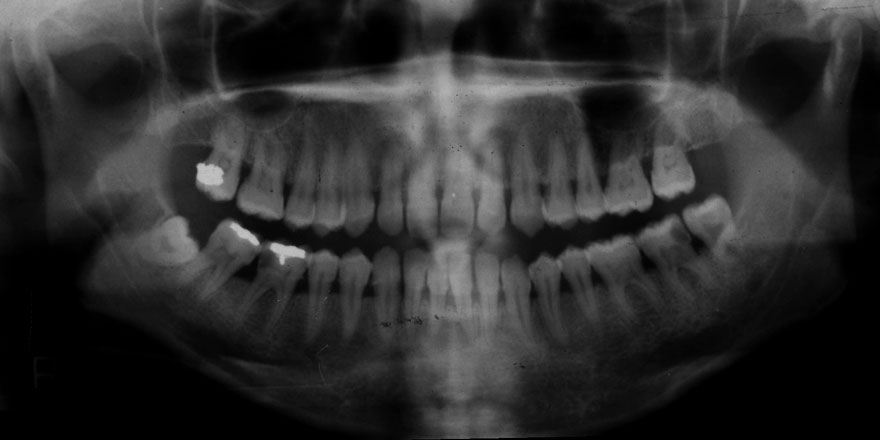

初診時 24歳 女性

初診時 24歳 女性 平均歯槽骨喪失量:1.57mm

19年後 43歳

平均歯槽骨喪失量:1.72mm

22年間喪失量:-0.15mm

年間喪失速度:-0.007mm

(ケア頻度:1.35ヵ月ごと)